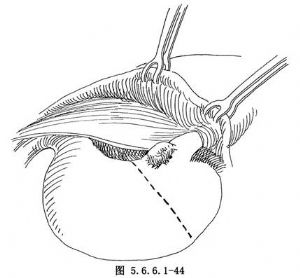

(4)距肿瘤下缘约5cm用自动胃肠缝合器(GIA)缝合、横断胃(图5.6.6.1-44)。用一把Kocher钳夹住胃之上切缘,而将下切缘再用中号线连续缝合加固,并用细丝线间断浆肌层缝合法包埋之(图5.6.6.1-45)。